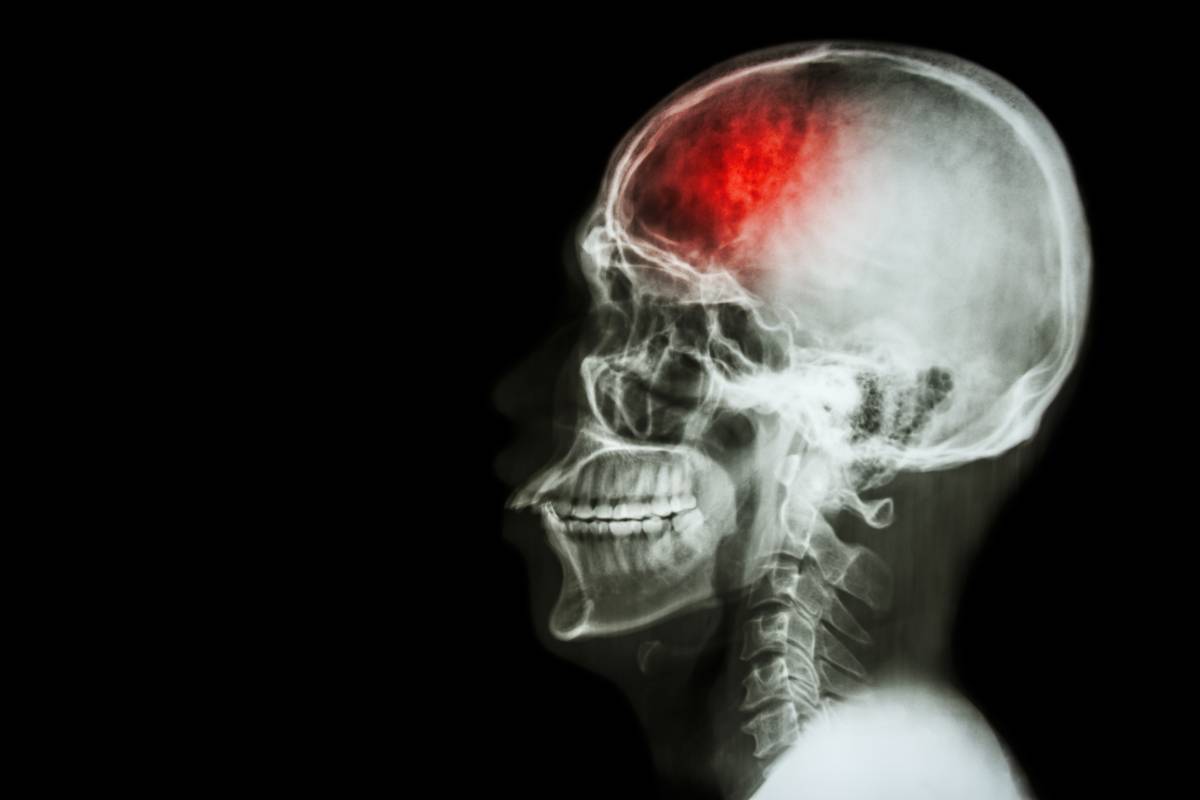

2021-09-08 13:19:00据资料报道,约70%的中风患者多在冬季发病,中风也被临床医生称为“冬季神经科的流行病”。中风又叫脑卒中或脑血管意外,是中医学对急性脑血管疾病的统称,包括脑血栓形成、脑梗塞、脑出血等。中风患者经及早抢救,大多能捡回一条命,可有3/4的患者会留下偏瘫、失语等不同程度的功能障碍,严重影响生活质量。因此,中风后尽早进行规范的康复治疗,能更大程度地恢复肢体功能。现在,临床多推荐中西医结合康复治疗方案,多管齐下,可取得较理想的康复效果。